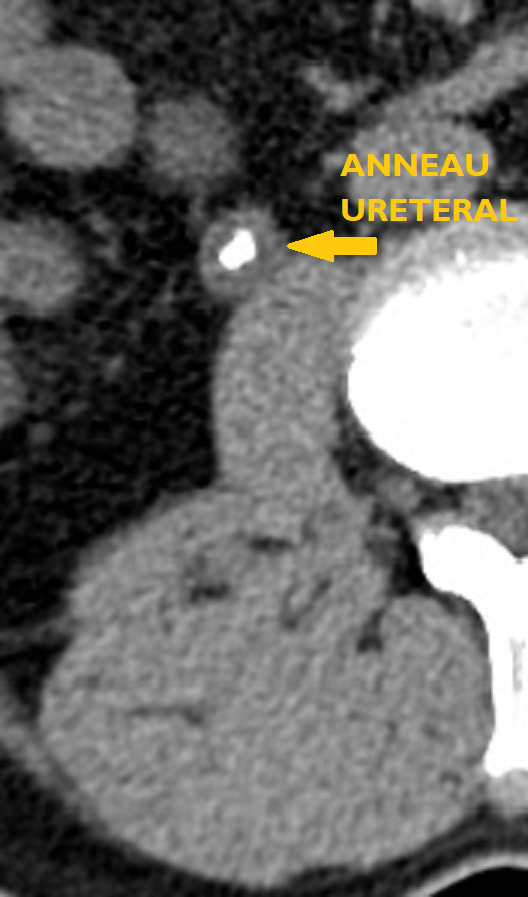

• en cas de calcul, de déterminer sa taille et sa localisation (impact pronostique important pour l’expul­sion spontanée ou le choix d’une technique interventionnelle) et leur nombre en cas de calculs multiples (fig. 1 et 2).

La sensibilité de l’échographie ou de l’abdomen sans préparation (ASP) isolément pour le diagnostic de calcul (respectivement de 80 et 90 %) ne les font recommander qu’en association (fig. 3). Pour l’imagerie initiale, cette association a été supplantée par le scanner abdominal compte tenu de sa rapidité de réalisation, pour un surcoût marginal, et de sa grande efficacité pour le diagnostic positif et différentiel. Le scanner a, en outre, un impact pronostique important pour l’expulsion spontanée (en fonction de la taille et de la localisation au diag­nostic) mais aussi le choix du traitement, la sensibilité aux ondes de choc étant à peu près corrélée à la densité tomodensitométrique.

Compte tenu du cumul d’irradiation, même de plus en plus faible grâce aux protocoles basses doses et sans injection (donc une seule hélice d’acquisition), l’examen ne peut être proposé à titre systématique itérativement pour le suivi ultérieur. En cas de doute diagnostique ou en l’absence de calcul, un complément d’imagerie avec injection de produit de contraste est recommandé.